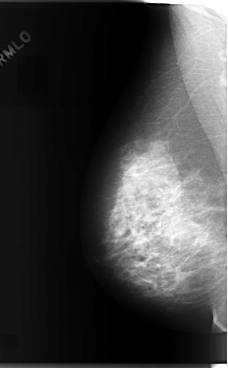

C_0070_1.LEFT_MLO

LEFT_MLO LINES 5904 PIXELS_PER_LINE 3504 BITS_PER_PIXEL 12 RESOLUTION 50 OVERLAY